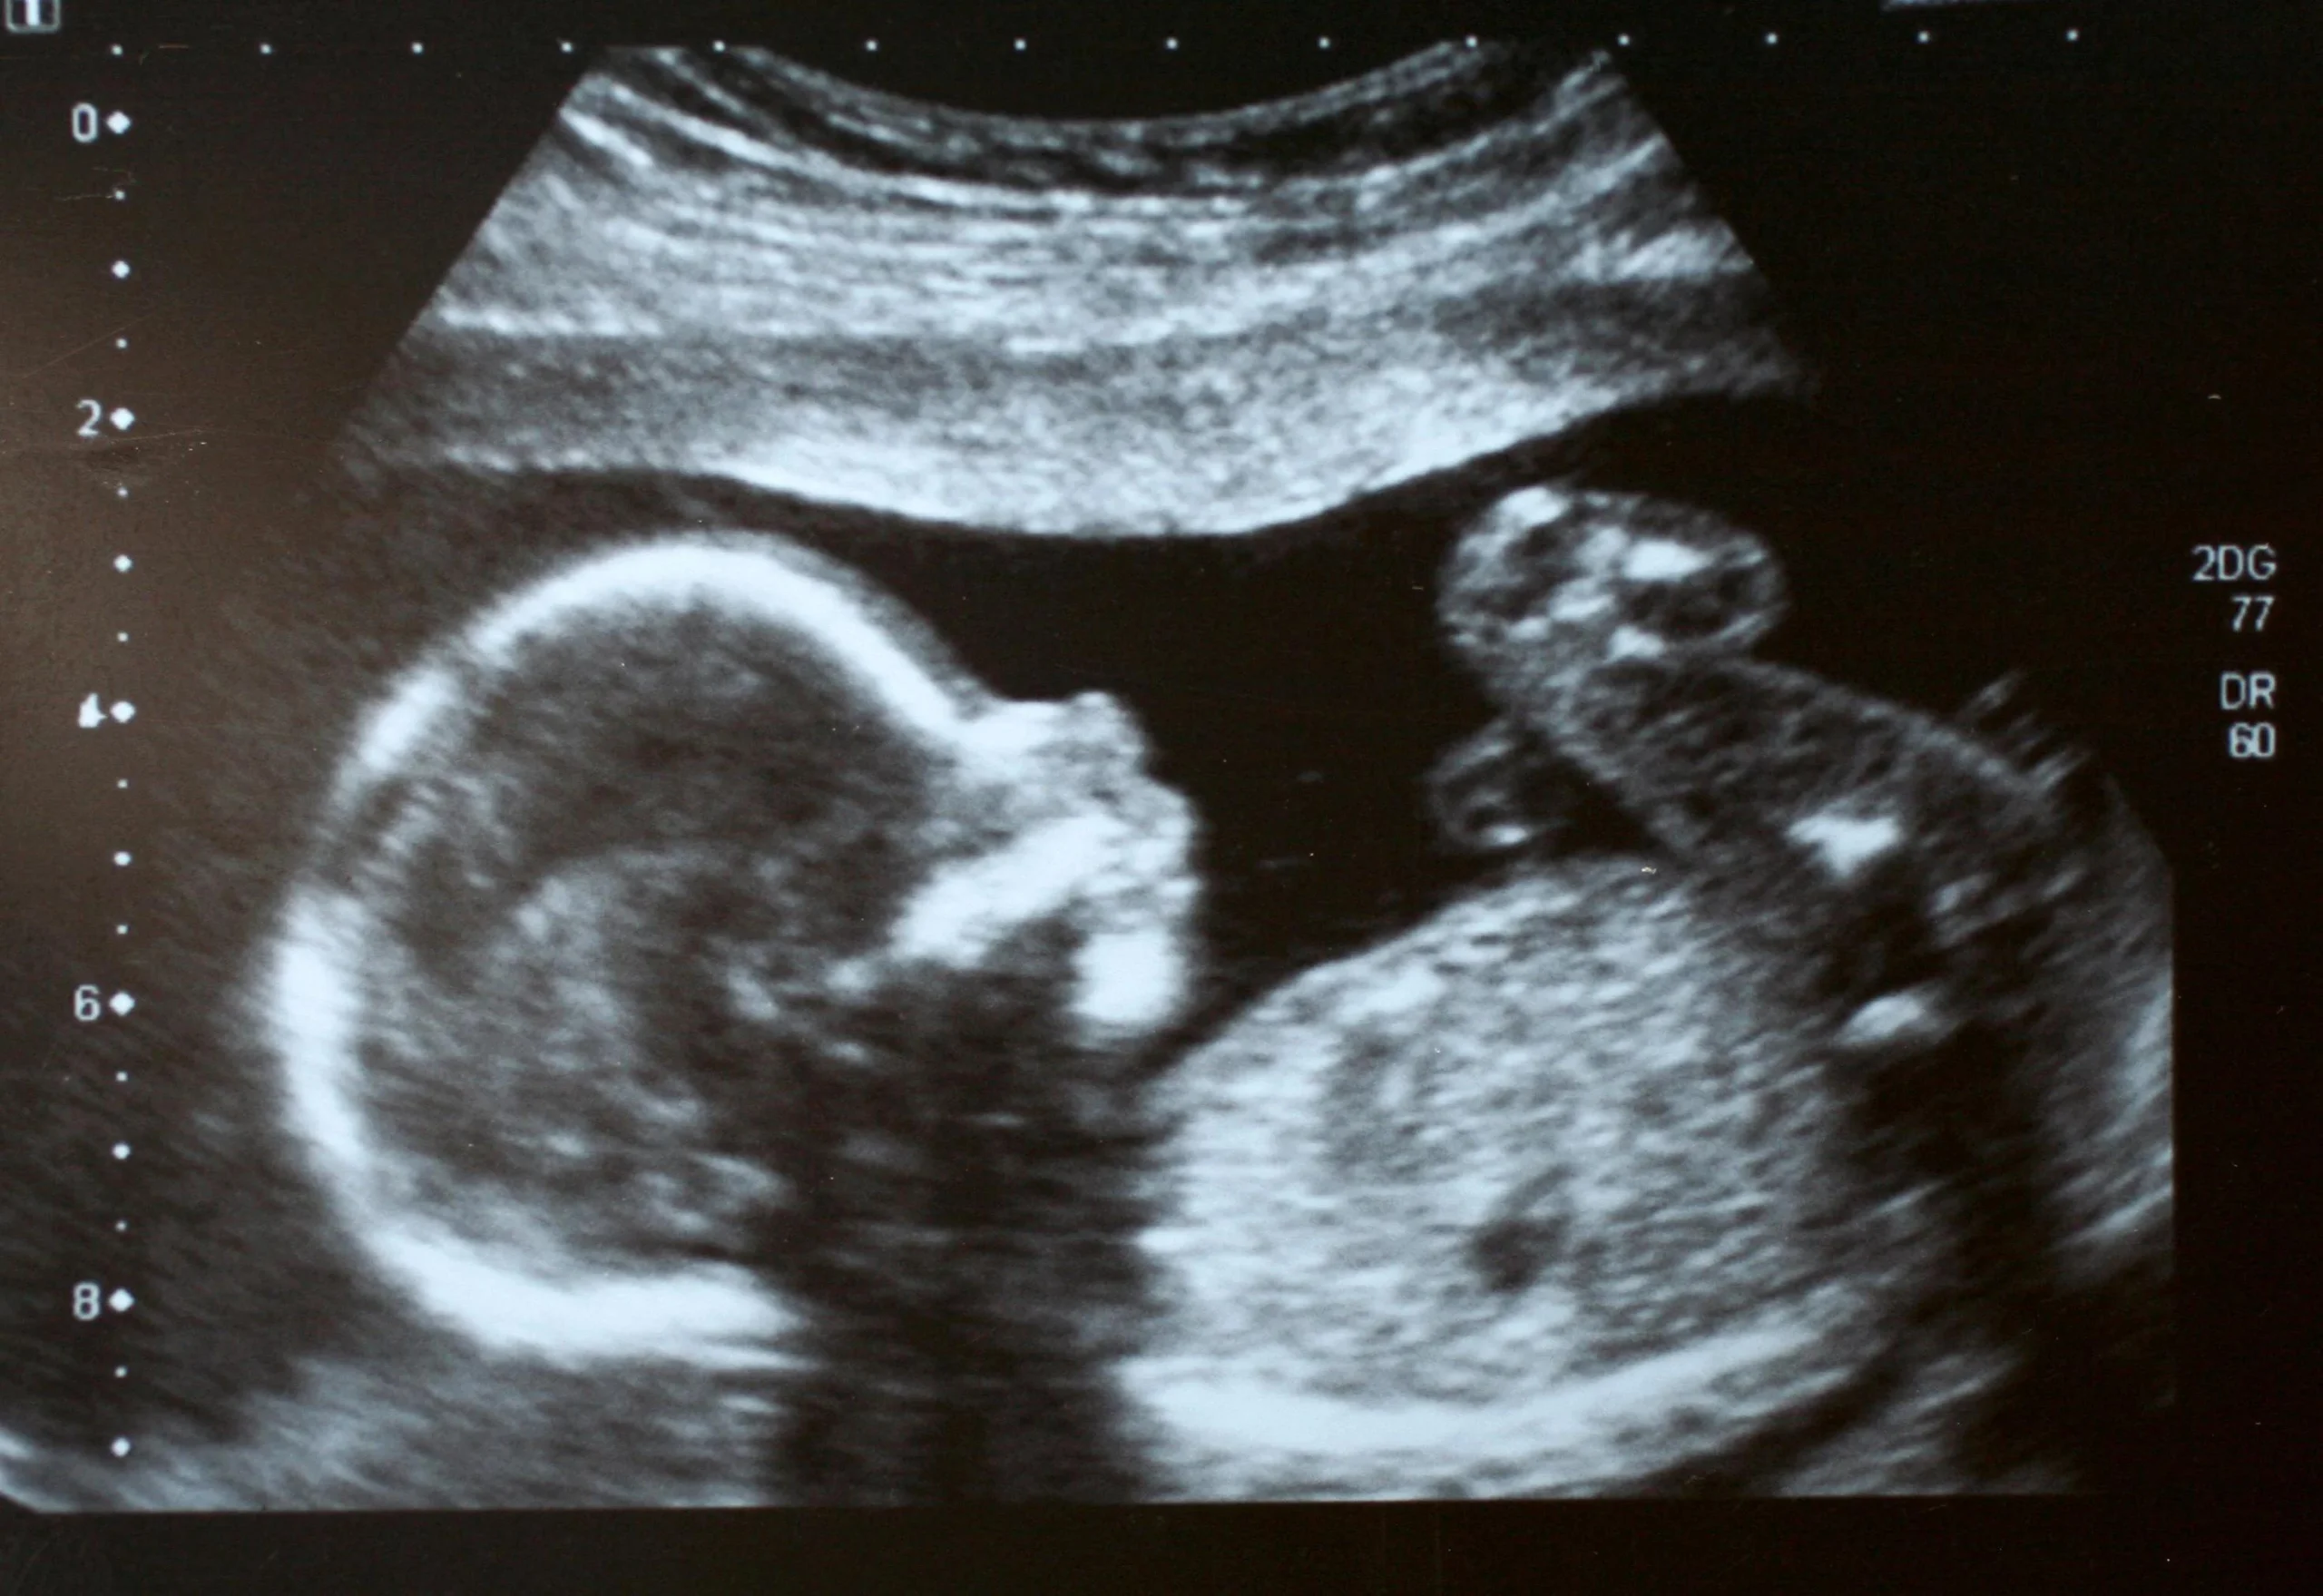

Der letzte Ultraschall in der Schwangerschaft dient in erster Linie dazu, die Entwicklung des Kindes und die Lage des Babys im Mutterleib zu beurteilen. Der Arzt oder die Ärztin untersucht dabei folgende Punkte:

- Größe und Gewicht des Babys: Der Ultraschall ermöglicht eine Schätzung des Gewichts des Kindes. Dies hilft, eventuelle Probleme wie eine zu geringe oder zu hohe Gewichtsentwicklung frühzeitig zu erkennen.

- Lage des Babys: Die Position des Babys im Mutterleib ist wichtig für die Geburt. Der Arzt oder die Ärztin kann feststellen, ob das Kind in Beckenendlage liegt, d.h. Mit dem Kopf nach oben, oder in Schädellage, d.h. Mit dem Kopf nach unten.

- Plazenta-Lage: Die Plazenta versorgt das Baby mit Nährstoffen und Sauerstoff. Der Arzt oder die Ärztin kontrolliert die Lage der Plazenta, um sicherzustellen, dass sie nicht den Geburtskanal blockiert.

- Fruchtwassermenge: Die Menge des Fruchtwassers ist wichtig für die Entwicklung des Kindes. Zu viel oder zu wenig Fruchtwasser kann auf Probleme hindeuten.

- Nabelschnur: Der Arzt oder die Ärztin prüft die Nabelschnur auf Auffälligkeiten, wie z.B. Verknotungen.

- Herzschlag des Babys: Der Herzschlag des Kindes wird kontrolliert, um sicherzustellen, dass es gesund ist.